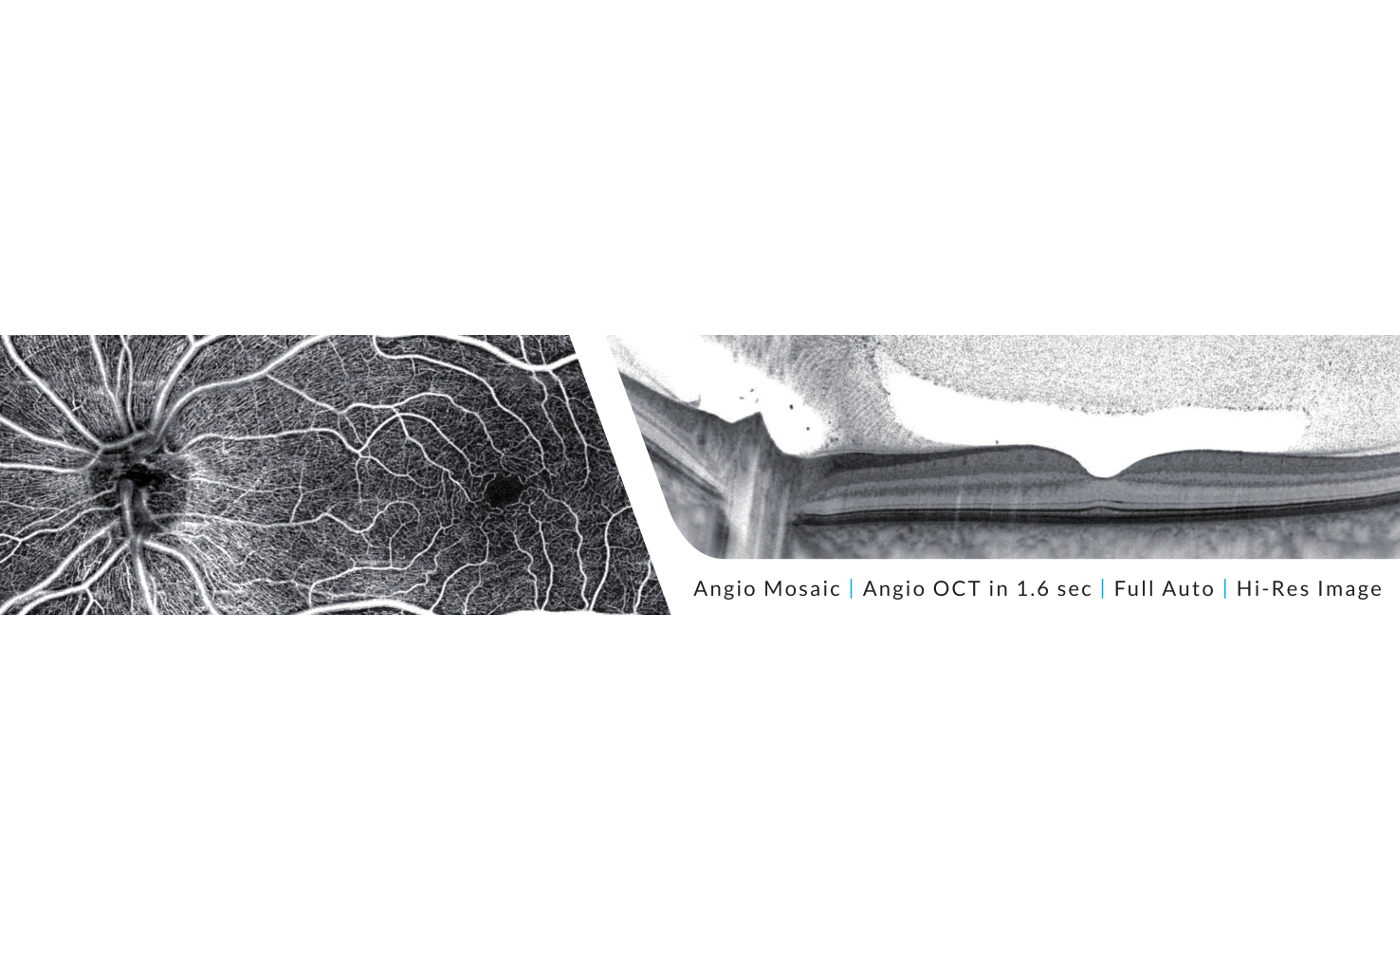

Ganglienzellenanalyse

Die Ganglienzellenanalyse des REVO OCTs liefert eine zusätzliche Glaukom-Analyse neben der konventionellen papillären retinalen Nervenfaserschichtdickenmessung.

Sie können zwischen 3 Analyseformen wählen NFL+GCL+ IPL Dicke, GCL+ IPL Dicke, NFL Dicke, zusätzlich unterstützt durch jeweilige NDBs.

Die Kombination von Ganglienzellenanalyse mit pappillärer retinaler Nervenfaserschichtdicke liefert einen besseren Biomarker für Ihr Glaukommanagement.